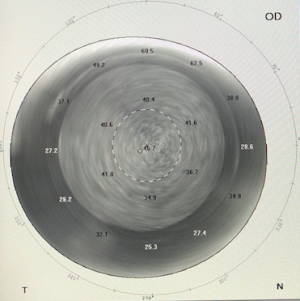

On exam, the vision can vary from mild impairment to hand motion vision. Intraocular pressure is increased but can be falsely measured normal in patients with IFS.[20][21][22] IOP should be measure peripherally with tonopen or other tonometers that are less likely to be influenced by corneal rigidity. Goldmann applanation tonometry of central cornea may provide falsely low IOP reading due to easy compressibility of fluid-filled space.[23][24] Patient may also have anterior chamber inflammation. Corneal haze is present at interface wound. The amount of fluid at interface wound is variable and an obvious fluid layer may not always be visible at the slit lamp.[25]

Diagnosis is through clinical history and slit lamp examination and confirmed with OCT. Ancillary testing such as OCT and corneal densitometry may aid with diagnosis and monitoring clinical course.[2][26]

It can be useful to confirm interface fluid accumulation in the cap-bed interface and monitor the clinical course.[2]

One study showed that corneal densitometry can be useful for evaluating and grading IFS.[2]